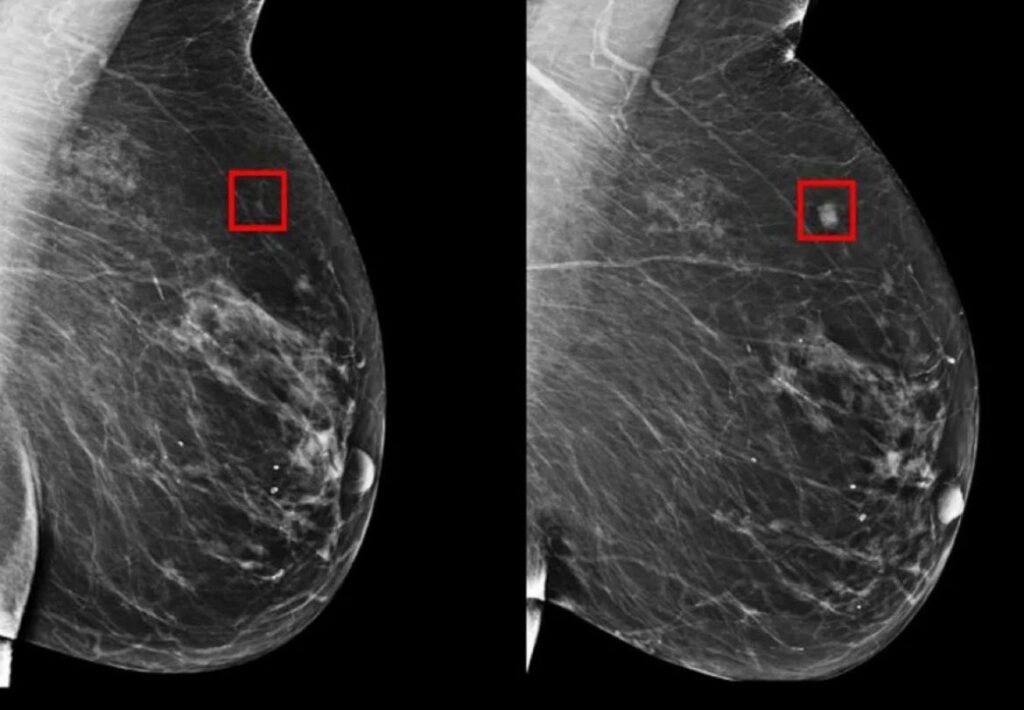

Chaque année, des millions de mammographies sont réalisées dans le monde, mais les protocoles actuels ne sont pas parfaits. Certains cancers passent sous le radar tandis que d’autres tests, parfois trop fréquents, engendrent des faux positifs, créant anxiété et coûts supplémentaires. C’est ici qu’intervient Mirai, un modèle de deep learning conçu pour optimiser la prédiction des risques de cancer du sein. En analysant des images mammographiques et des facteurs de risque potentiellement absents, Mirai peut fournir des prédictions précises sur plusieurs années (jusqu’à cinq ans).

Conçu par une équipe de chercheurs du MIT et validé par des tests sur des données de l’hôpital général du Massachusetts (MGH), de l’hôpital Karolinska en Suède et de l’hôpital Chang Gung Memorial à Taïwan, ce modèle a montré une capacité unique à fonctionner efficacement sur des systèmes de mammographie variés, en s’adaptant aux différences d’appareils et aux données manquantes. Un atout crucial dans les contextes cliniques où chaque variable compte.

Le succès de Mirai repose sur des résultats impressionnants. Comparé à des modèles plus anciens tels que Tyrer-Cuzick, Mirai a démontré une performance nettement supérieure, avec des AUC (Area Under Curve) atteignant jusqu’à 0,81, contre des scores bien inférieurs pour les concurrents. Cela signifie qu’il identifie avec plus de précision les patientes à haut risque, permettant ainsi une détection précoce des cas de cancer et, potentiellement, une réduction des décès.

Sur un échantillon de patientes du MGH, 41,5% de celles qui développeront un cancer dans les cinq ans ont été correctement identifiées comme étant à risque, contre seulement 22,9% pour le modèle Tyrer-Cuzick. Une amélioration significative qui pourrait transformer la manière dont les programmes de dépistage du cancer sont réalisés dans le monde.